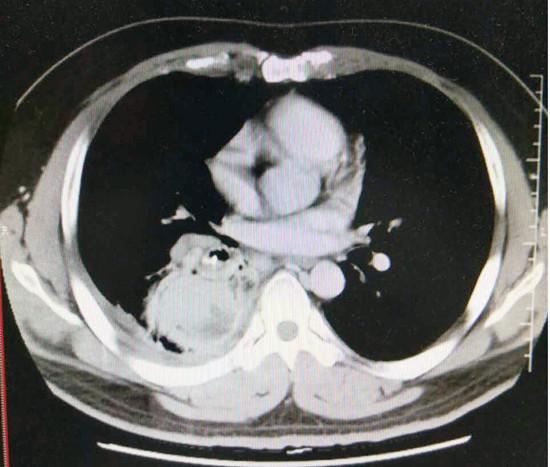

(胸部CT显示右下肺支气管内高密度异物,右下肺阻塞性肺炎并脓肿形成)